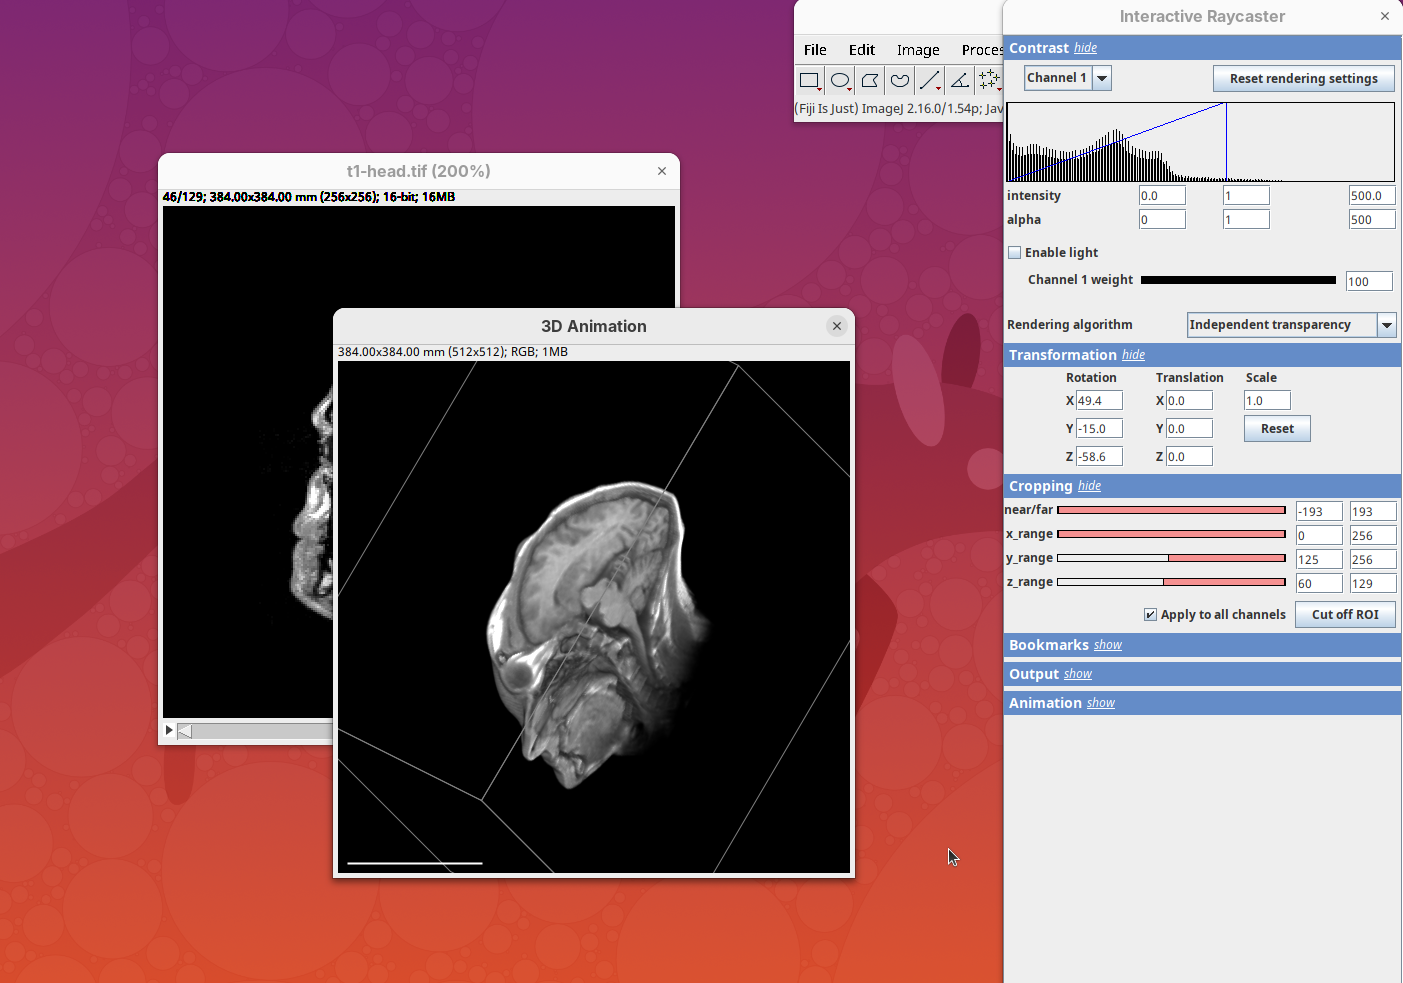

3Dscript

3Dscript is a GPU-accelerated Fiji plugin to generate animations of 3D/4D data (Schmid et al. 2019). It supports stacks with multiple channels and timepoints, has several options to control the rendering appearance, allows custom transformations and cropping of the data, and generates animations using a natural language, which is great to have precise control over the animation. 3Dscript is also incredibly fast to generate the animations and doesn’t require a lot of memory since the datasets can be opened as virtual stacks (more about this below).

This tutorial covers the basics for generating animations for 3D and 4D datasets. For more detailed information and documentation please refer to 3Dscript’s wiki.

To get started, make sure the head dataset is still open.

- Go to

Plugins>3Dscript>Interactive Animation.

Two new windows will open: 3D Animation with the initial rendering of the data and Interactive Raycaster with all the fields to control the rendering parameters.

Contrast

The Contrast section shows a histogram of pixel intensities of the image for each channel, which we can choose using the dropdown menu. We can set the minimum, gamma, and maximum values for the intensity and alpha (transparency) properties of each pixel. The weight option controls the general opacity of the channel (0=invisible, 100=visible). There’s also more advanced options like lighting and rendering algorithm which we’ll simply use the default states as they are usually good for most use cases.

Adjusting the intensity and alpha values is the most impactful way to improve the 3D rendering. With the intensity setting we can define which pixel value in the image corresponds to total black (minimum) and which corresponds to total white. It’s the same as in the standard Brightness & Contrast tool. By default, 3Dscript will load these values from the original stack. In this case, it loaded min=3 and max=521.

Let’s change these values to see how it impacts the 3D rendering.

- Change the intensity minimum to

250.

You will see that the darkest parts of the rendering will become even darker and no longer visible. We are losing real information from the data; we do not want that.

- Set the

minto0, for now. - Then, change the

maxto250.

The brightest parts of the rendering will become all white. It is so bright that we can no longer resolve details of the surface. We are losing information and also do not want that.

- Set the

maxto500.

Note that when you change an intensity value, the min/max black line in the histogram moves. You can also grab the line and move it manually to change the values.

The blue line represents the alpha values. In 3D rendering, a pixel has a transparency value linked to its intensity. The alpha min defines the value for full transparency and the max the value for full opacity.

- Set the alpha

minto250.

This will make darker pixels more transparent and information gets lost.

- Set it to

0.

By default 3Dscript sets the gamma value of alpha to 2.0. That’s a good default for fluorescence microscopy (see the next dataset below), but since this is MRI data, we need to tweak it a little differently.

- Set the alpha gamma value to

1.0.

Note that this improves the visualization as the head’s surface becomes better visible.

- Now set the alpha

maxto250.

The surface will become even more solid because we are defining that pixels that have a value above 250 will be fully opaque.

- To compare, set alpha

maxto5000.

You will notice that the sample will become more transparent. Even the brain inside the skull will be visible.

- Set alpha

maxback to500.

Generally, setting the intensity and alpha to the same values is a good starting point for optimizing the rendering.

Transformation

The transformation menu has controls for rotating, translating, and scaling the sample. We can either add values or manually interact with the 3D Animation window to reorient the sample. Let’s try the latter.

- Left-click on the head and move it around.

That’s a great way to see your sample from different angles. And note that the values in the Transformation panel get updated every time you move the sample interactively. In this way you can roughly position the sample and then check and update the precise values for the target transformation.

- Press

Resetand change theRotation Yto180to look at the right side of the head.

- Now change

Scaleto5andTranslation Xto-500to focus on the nose.

- Press

Resetto return the sample to its original position.

Cropping

Another useful 3Dscript option is the ability to crop the bounding box to show the inside of the sample. We can do it in the XYZ directions or in the near/far axis, defined from the user point of view.

- Set the Z range minimum value to

60(you can also drag the slider) to slice the sample through the Z axis.

- Now rotate the sample to see the cropped region from other angles.

- Set the Y range

minto125and rotate around.

- Finally, reset the position and cropping parameters and set the Near/Far minimum to

0and move the sample around to see the dynamic reslice of the sample with this cropping parameter.

- Reset transformations and cropping parameters.